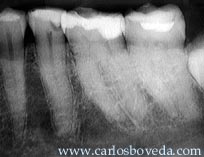

Estando en su consulta dental, y recibiendo una preparación en el primer molar inferior izquierdo, la paciente manifestó un dolor continuo e intenso en este molar que no puedo ser disminuido con la anestesia del área. Habiéndose producido una exposición pulpar , la paciente nos es referida. Radiográficamente puede evidenciarse la proximidad de la base al espacio pulpar en el primer molar.

Su Odontólogo está consciente del área radiolúcida coronal del segundo premolar ) posible pérdida de sustancia calcificada compatible con caries) y nos hace mención de esta situación, para no preocuparnos en relación a este diente y hacernos saber que va a ser restaurado próximamente.

Coincidimos con la opinión de la mayoría de los participantes de este foro, en el sentido que las evidencias muestran un compromiso endodóntico no solo en el primer molar, sino también en el segundo premolar inferior izquierdo.

El molar continua mostrándose sensible a las pruebas de vitalidad y percusión, pero el premolar responde muy levemente a las pruebas de vitalidad, más si se encuentra sensible a la percusión vertical. Esto nos confirma el compromiso endodóntico de este diente también.

Las imágenes radiográficas finales permiten evaluar el tratamiento realizado.